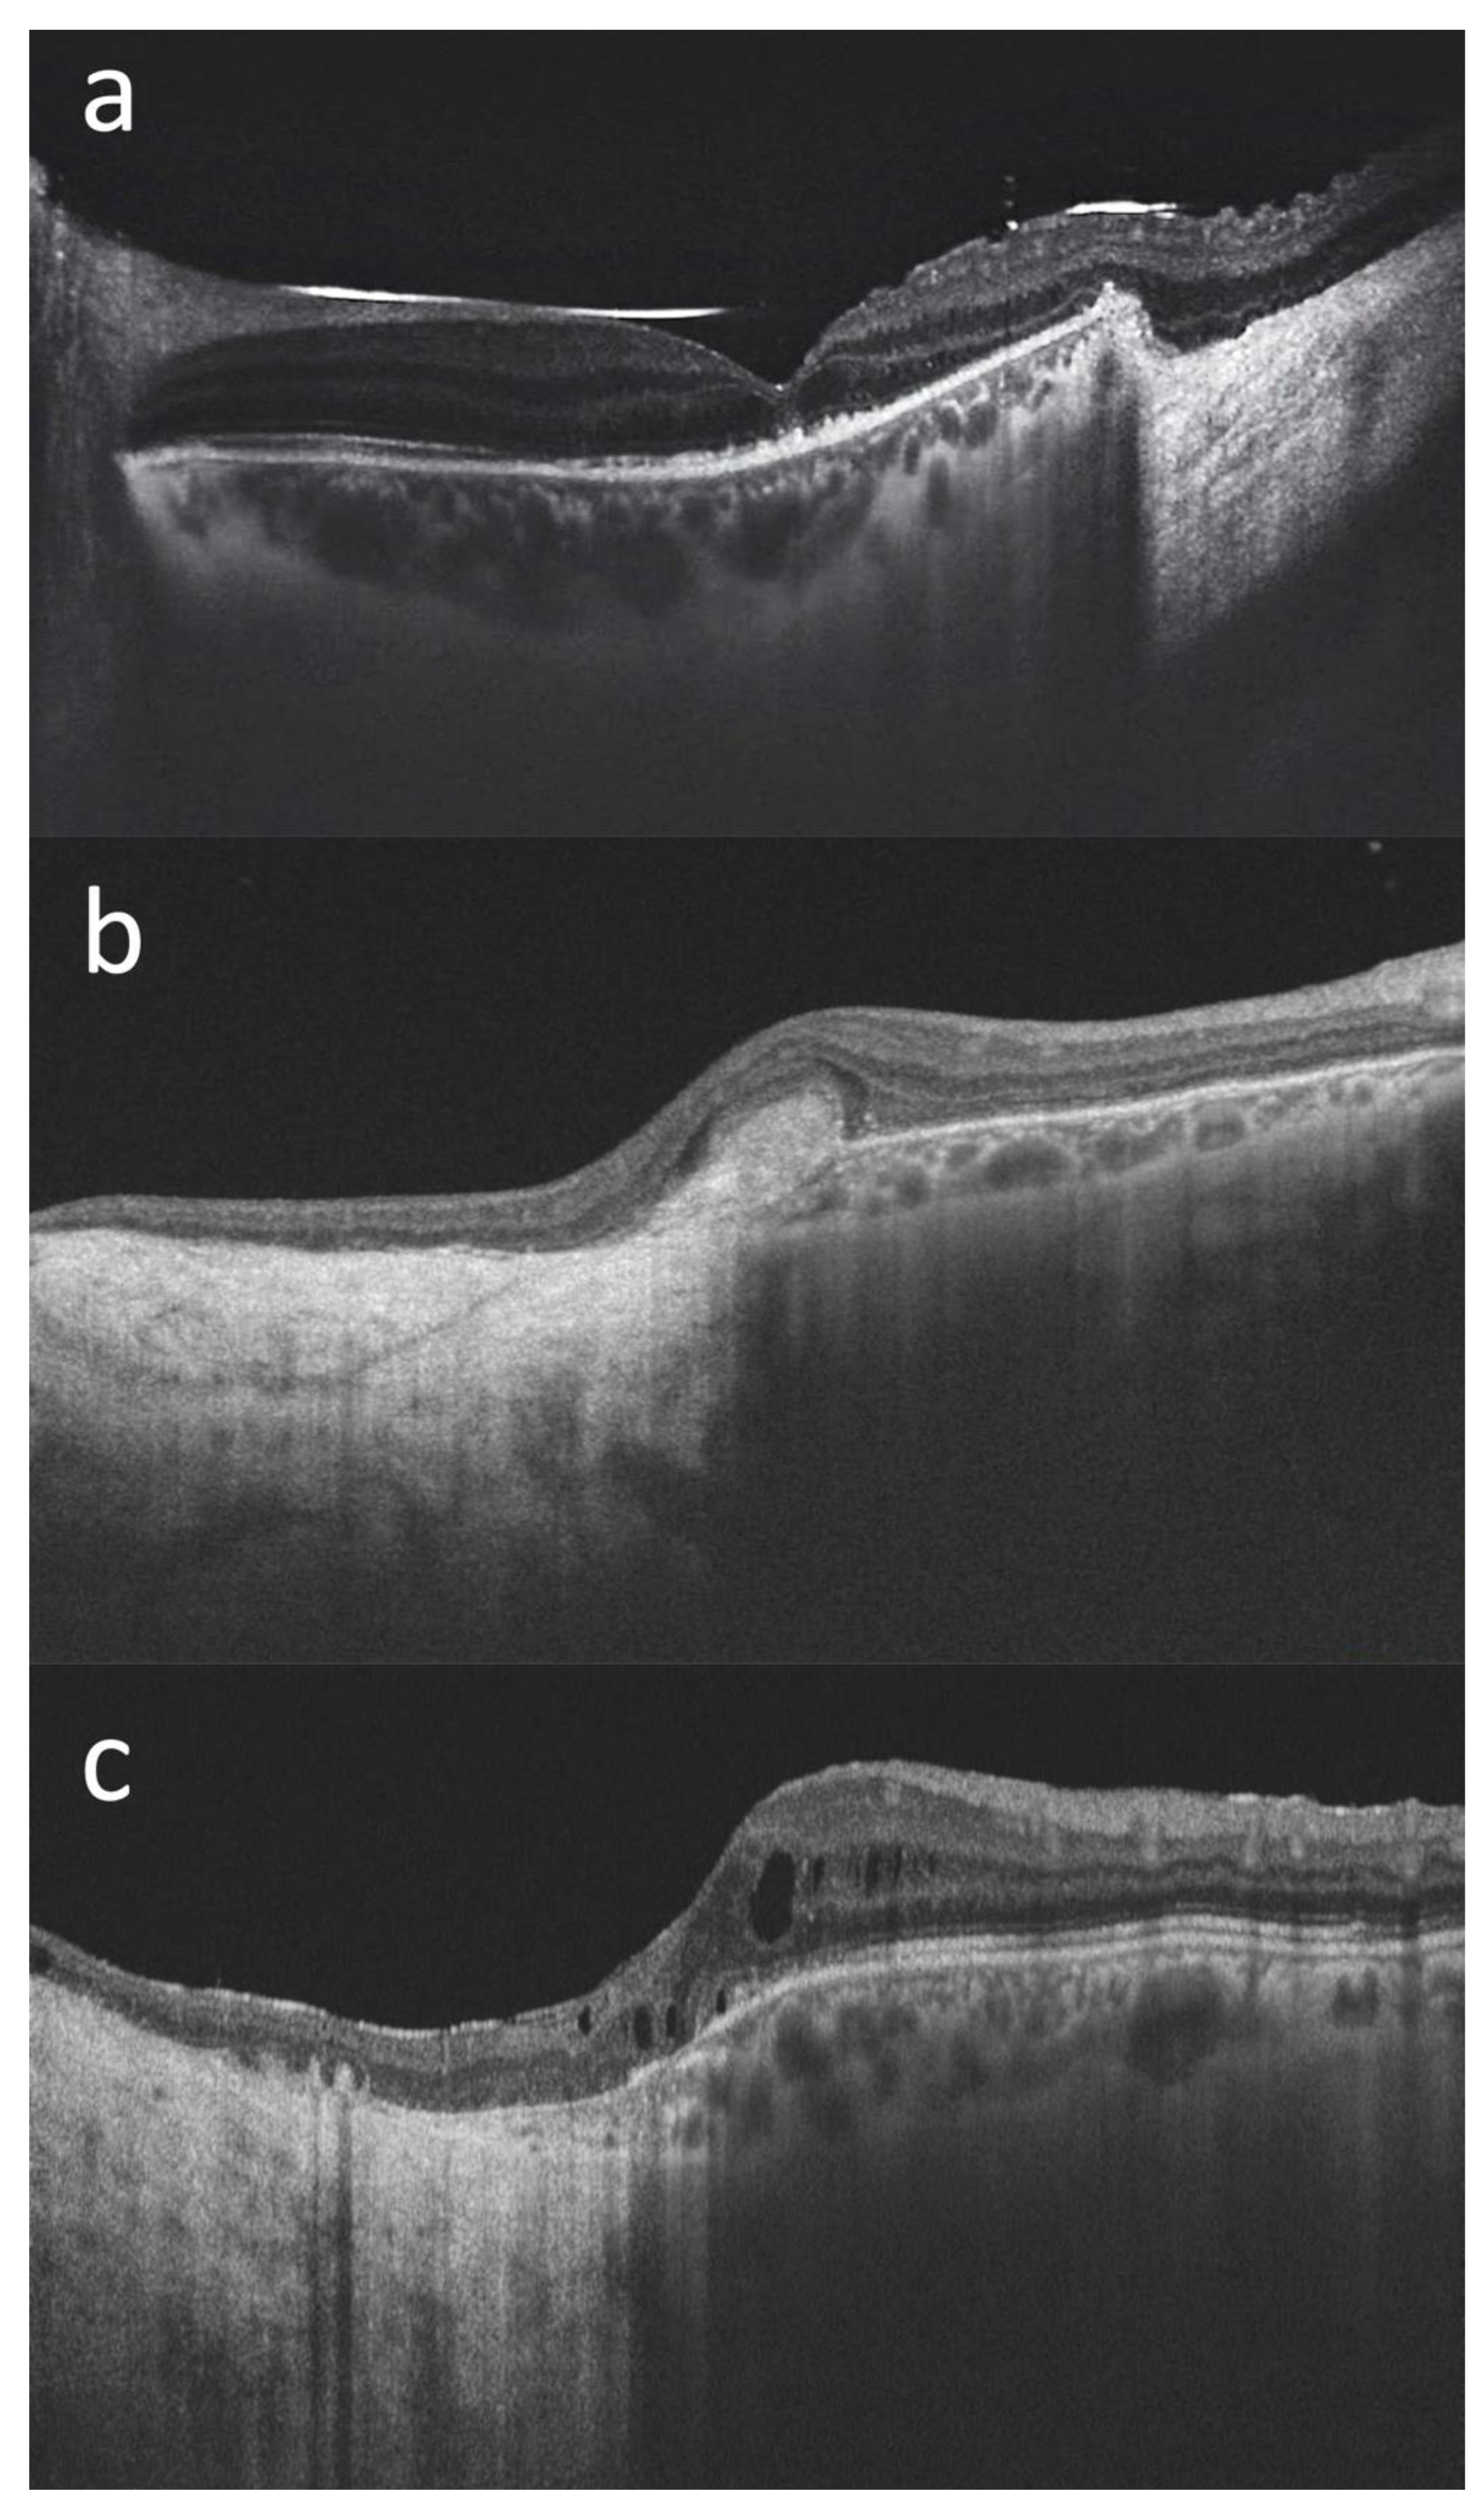

The mean BCVA at last follow-up visit was 20/70 (ranging from counting fingers to 20/20). Mean IOP at last follow-up was 16 mmHg, with three out of fifteen patients on IOP-lowering medication (case #6, case #8 and case #14). When the lesions extended posteriorly, surgical resection involved the macular region. In these cases (for example case #1 and case #15—Figure 3), it was still possible to maintain a useful visual acuity.

Figure 3.

Macular optical coherence tomography (DRI OCT Triton; Topcon Corporation, Tokyo, Japan) scans of three patients with choroidal melanoma involving the posterior pole who have undergone endoresection with preservation of the retina overlying the lesion ((a): case#1, (b): case #2, (c): case #15). We can see the transition from the normal retina and choroid to the surgical choroidal coloboma, with the retina directly overlying the hyperreflective sclera, in all cases. The foveal retinal profile is relatively well preserved in (a), while it is altered in (b,c) where the surgical coloboma reaches the macula. In case (b) we can see an hyperreflective subfoveal fibrous scar. In case (c), a mild cystoid macular edema is noticeable. The silicone oil meniscus and irregularities of the subfoveal outer retinal layers are also visible in (a) (the scan was acquired prior to the silicon oil removal). In all three cases a useful visual acuity was maintained at the last follow-up visit (20/100 in case #1, 20/125 in case #2, and 20/32 in case #15).